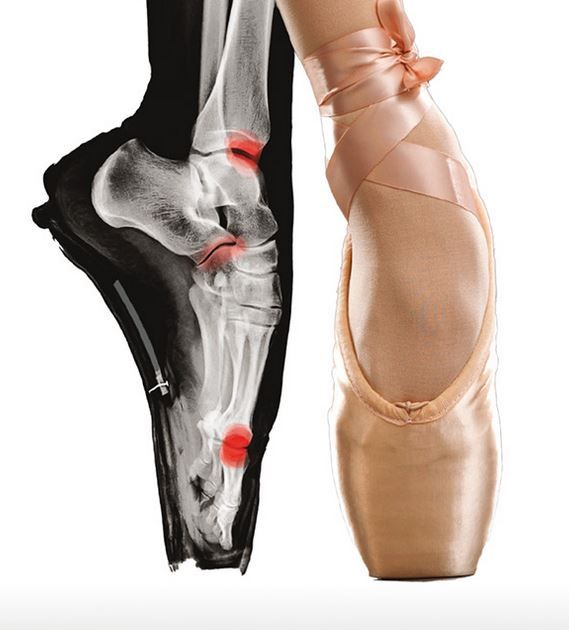

Die Behandlung entzündlich rheumatischer Erkrankungen ist mit einer Ballettaufführung durchwegs vergleichbar. Es bedarf viel Training und Ausdauer, eine komplexe Vernetzung unterschiedlicher (Be)handlungsabläufe und eine genaue choreographische Abstimmung mit seinen (interdisziplinären) Partnern. Durch die enorme Geschwindigkeit der Weiterentwicklung von Forschung, Diagnostik und Therapien entzündlich rheumatischer Erkrankungen muss fortwährend trainiert werden, um im Spitzenfeld mittanzen zu können.